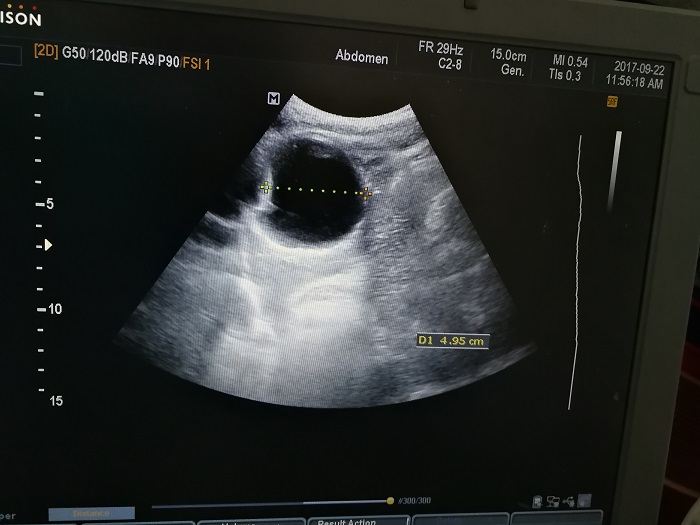

扎西(化名),男,15歲,包蟲病篩查陽性,牧區(qū)孩子,家里有牦牛20頭、羊200只,狗1條,牛羊自家屠宰,飲用河水。

●革吉縣初級中學篩查點 · B超現(xiàn)場圖片

除了包蟲病篩查外,連續(xù)三天的學校體檢我醫(yī)療隊發(fā)現(xiàn)腎積水、腎囊腫、腎結石的學生患者較多,我們將體檢到的相關臟器疾病同時間反饋給了班主任,讓他們密切觀察病情,及時通知家長。劉冬梅醫(yī)生建議,學校要組織學生多飲水,同時多加觀察本地水質(zhì)情況。

本次篩查,革吉縣初級中學共篩查學生498例,陽性3例,疑似2例。